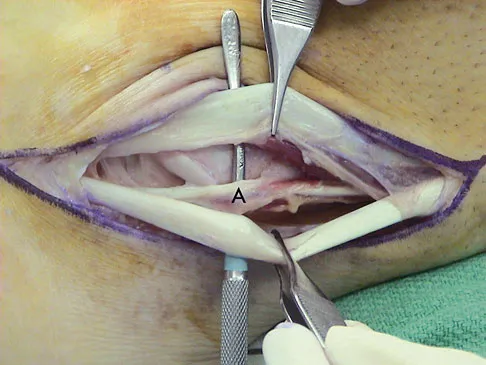

Question 82

A 35-year-old man is seen for evaluation of his left ankle following multiple previous ankle sprains and frequent episodes of the ankle giving way. Examination reveals marked laxity about the lateral ankle with associated tenderness along the peroneal tendons. Physical therapy, anti-inflammatory drugs, and supportive bracing have failed to provide relief. An MRI scan shows peroneal tenosynovitis and a possible tear. He elects to undergo a peroneal tendon repair and lateral ligament reconstruction. Which of the following best describes the structure labeled "A" in Figure 45?

Explanation